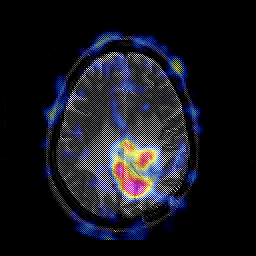

Glioblastoma multiforme overlay -- Slice #36

[Home][Help][Clinical][Tour 1][Tour 2][Tour 3] Slice 36